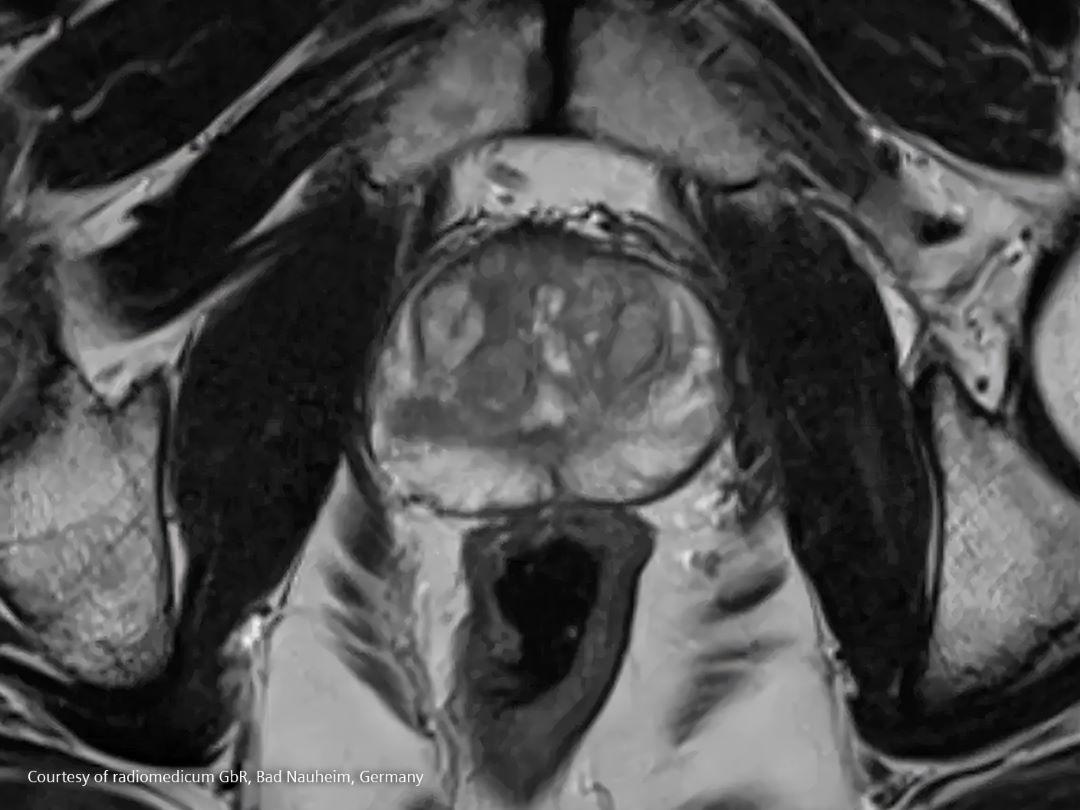

Diagnosis and Staging

What if a doctor suspects a patient might have prostate cancer?

During diagnosis, a patient will be asked about any symptoms as described above and about possible risk factors including his family history. In case of any suspicion, the doctor might order some tests.